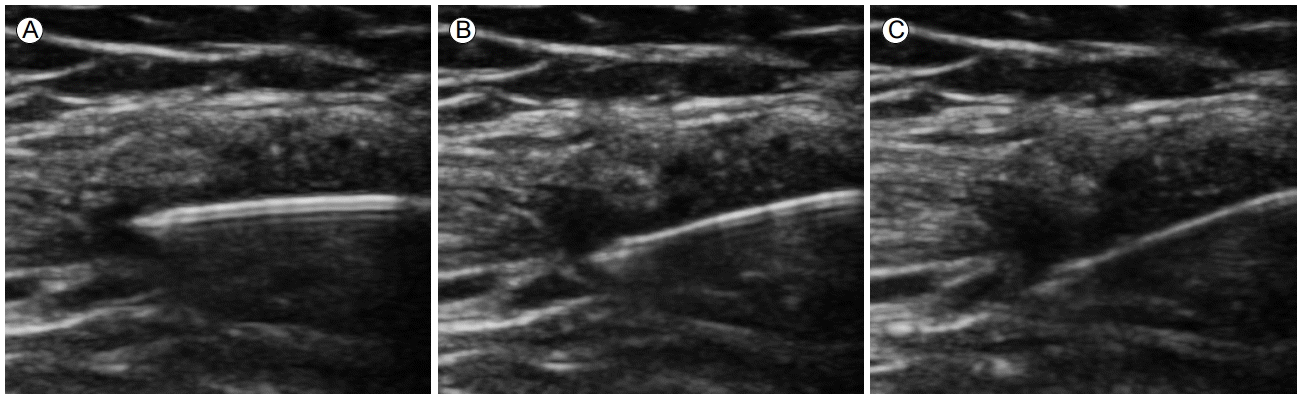

Figure 1.

In-plane approach to position the needle under US guidance. (A–C) US detection of a metallic needle at different angles relative to the US beam. With increasing obliquity, the needle becomes less evident and detection of its tip is uncertain. US, ultrasound.

초음파 유도 방법에는 간접법과 직접법의 두 가지의 접근법이 있다. 간접법은 초음파로 스캔하면서 바늘이 들어갈 최적의 위치를 선정한 후에 그 위치의 피부에 표시만 하고 실제 바늘을 주입할 때는 초음파를 사용하지 않는 방법이다. 이 방법은 베이커낭종과 같이 피부 표면에 가까이 위치한 큰 구조물이나 삼출액이 많은 무릎관절과 같은 큰 관절에 적합한 방법이다. 바늘이 들어갈 보다 정확한 위치를 찾기 위해서 페이퍼 클립을 활용하기도 한다[14]. 직접법은 시술을 하는 동안 초음파로 바늘의 위치를 실시간으로 확인하면서 바늘을 주입하는 방법이며, 촉진이 쉽지 않는 깊은 구조물을 목표로 할 때 유용하다. 이 방법은 탐촉자를 잡은 손과 바늘을 잡은 다른 손을 동시에 조화롭게 다루는 능력을 갖기 위한 연습과 경험을 요구한다.초음파 유도시 목표물의 크기와 깊이에 따라 바늘은 탐촉자의 장축에 평행하게 진입하거나(in-plane), 또는 직각으로(out-of-plane) 진입할 수 있다. 바늘이 탐촉자와 평행에 가까울수록 바늘을 더 잘 관찰할 수 있으며, 후방 반향(posterior reverberation)을 보이는 고에코의 선명한 선으로 나타난다. 한편, 탐촉자와 바늘 사이의 각도가 가파를수록 바늘은 잘 보이지 않게 된다(Fig. 1). 반면, 바늘이 탐촉자의 장축에 대해 직각으로 접근하게 되면, 바늘은 고에코의 하얀 점으로 관찰된다(Fig. 2). In-plane 접근법이 대부분의 초음파 유도에 사용되지만, 표층의 작은 관절에는 out-of-plane 접근이 보다 더 용이할 수 있다. 바늘을 삽입한 후에 항상 종단면과 횡단면을 함께 스캔하면서 목표와 바늘 끝의 위치 관계를 확인하고 중재술을 진행한다[15].시술 중 바늘의 시인성을 높이기 위해서는 병변의 깊이에 따라 적당한 초음파 주파수를 선택한다. 그리고 주사 바늘이 항상 초음파 빔과 수직이 되도록 노력하며 시술 중 주사침의 방향이 탐촉자 축과 정렬되어 있는지 확인하면서 시술을 시행한다. 바늘 끝을 잘 보기 위해서는 바늘 끝 경사면(bevel)이 항상 초음파 빔 방향을 향하게 하고 바늘을 빠르게 움직이거나 흔드는 것(jiggling)이 도움이 될 수 있다[16]. 몇몇 저자들은 소량의 공기를 주입하는 방법을 제안하기도 했지만, 공기는 오히려 밑에 있는 구조물을 가려 시술을 방해하는 요인이 될 수 있다[17].- 장비와 시술 준비